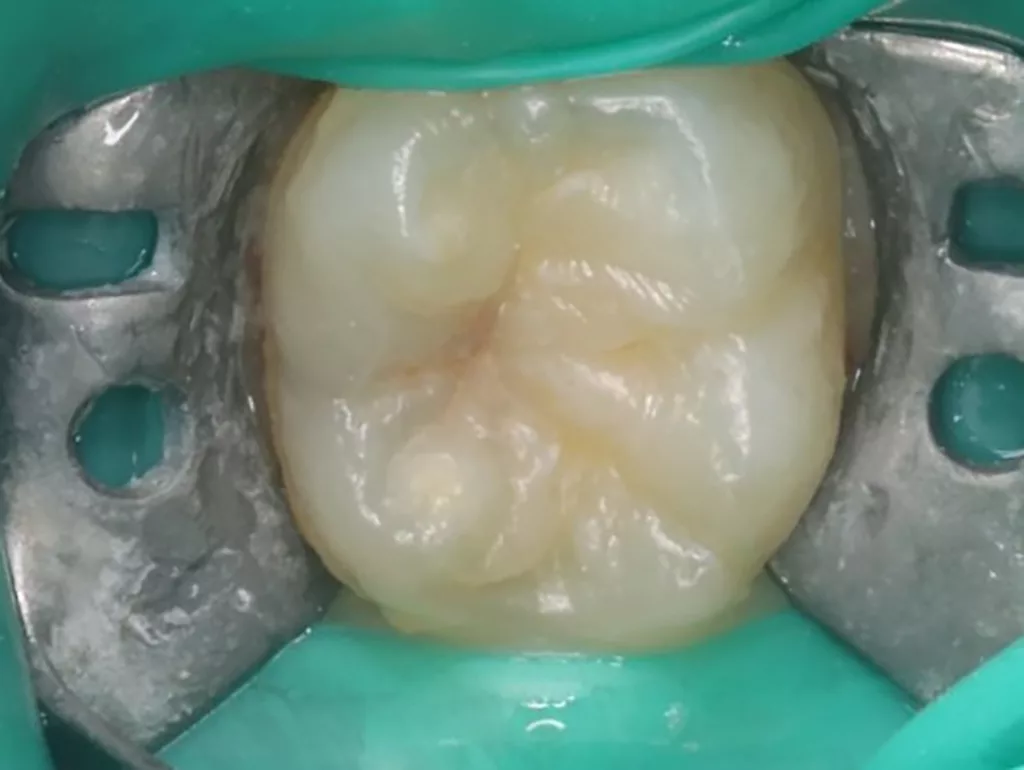

Das siebenjährige Mädchen wurde von einer Kollegin zur Behandlung einer atypischen intrakoronalen Aufhellung im Kronenbereich des nach Durchbruch befindlichen symptomatischen Zahnes 46 überwiesen (Abb. 20). Anamnestisch bestanden seit zwei Tagen kurzintervallige Spontan- und Nachtschmerzen, die mit Ibuprofen 40 mg/ml Kindersirup behandelt wurden. Das Röntgenbild zeigte einen umfangreichen runden Dentindefekt unter intaktem Zahnschmelz, der bis in das Pulpakavum reichte. Daraus ergab sich die Verdachtsdiagnose PEIR des Zahnes 46 (Grad 3 der Läsion nach Seow) in Kombination mit einer akuten Pulpitis. Nach Leitungsanästhesie am Foramen mandibulae mit Septanest 1/100 000 (Septodont, Frankreich) und STA-System (Milstone Scientific, USA) konnte der Zahn mithilfe von Kofferdam (Klammer U67, KSK Dentech, Japan) gut isoliert werden (Abb. 21). Um die ursprüngliche Zahnanatomie zu imitieren, wurde ein Okklusalstempel aus dem flüssigen Kofferdam OpalDam (Ultradent, Frankreich) und einem Microbrushapplikator angefertigt.

Der PEIR-Defekt schimmerte unter der lingualen Querfissur deutlich dunkler durch (Abb. 21), sodass die Entscheidung getroffen wurde, den Defekt an genau dieser Stelle zu eröffnen (Abb. 22). Das resorbierte intrakoronale Weichgewebe, das die Läsion nur zum Teil füllte, konnte dann gut visualisiert werden (Abb. 22). Kariös verändertes Dentin wurde nicht gefunden. Nach Eröffnung des Pulpahorns sah die Pulpa blass und avaskulär mit Anzeichen einer geringen Blutung aus (Abb. 23). Die komplette Kronenpulpa wurde bis zur Höhe der Kanaleingänge mit einem runden Diamantbohrer unter Wasserkühlung entfernt. Vor und nach der Prozedur wurde die Läsion zuerst mit 1%igem NaOCl und anschließend mit physiologischer Kochsalzlösung gespült. Die Blutung stoppte innerhalb von zwei Minuten vollständig, die Wurzelpulpa erschien gesund, regulär vaskularisiert und sauber (Abb. 24). Es wurde eine reversible Pulpitis diagnostiziert. Die Abdeckung der Wurzelpulpa erfolgte mit einem hydraulischen Kalziumsilikatzement (Rootdent, Technodent), der mit dem Glasionomerzement Fuji II LC (GC, Japan) als temporäre Füllung abgedeckt wurde. Die Platzierung des MTA-Zements wurde abschließend mittels einer Röntgenaufnahme überprüft (Abb. 27). Nach zwei Wochen war die junge Patientin komplett beschwerdefrei. Unter erneuter Trockenlegung mit Kofferdam wurde die adhäsive koronale Restauration mit Komposit Estelite ASTERIA OCE, A2B und Universal Flow AO2 (Tokuyama, Japan) mithilfe eines vorab angefertigten Okklusalstempels erstellt (Abb. 25 und 26). Ein Jahr später kam die Patientin beschwerdefrei zur Nachkontrolle. Das Röntgenbild (Abb. 28) zeigte keinen pathologischen Befund sowie eine physiologische Weiterentwicklung des Wurzelwachstums in Länge und Dicke der Wurzelwände.